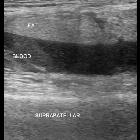

The FBI sign is an acronym referring to the components that form a lipohemarthrosis. It stands for:

- fat

- blood

- interface